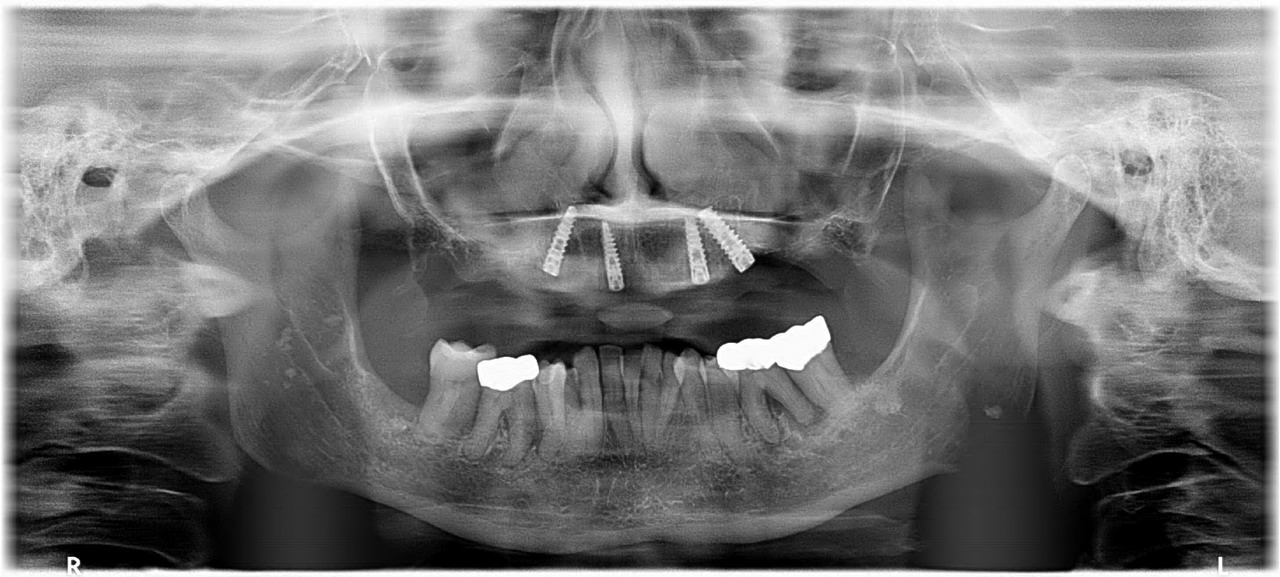

Dott. Romano Caso 1

Caso 1